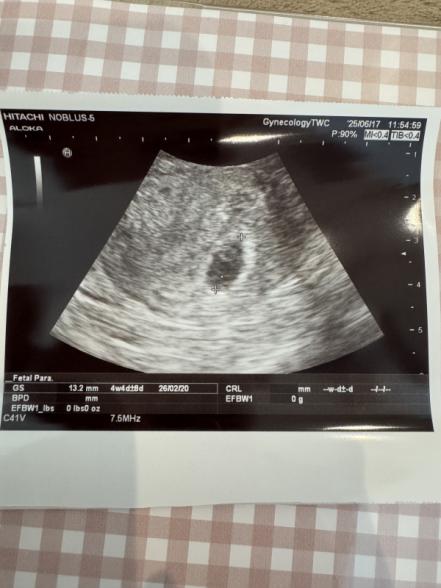

初めまして。不妊治療で4回目の胚盤胞を移植した者です。3回は流産してしまい、ようやく辿り着いた4回目。5月22日に脱出途中6日の胚盤胞ABを移植して、6月2日に妊娠判定hCG174.2でした。6月10日に胎盤が見えましたが6.4mmと小さく、6月17日には13.2mmで倍近くに成長し卵黄嚢も見えましたが、赤ちゃんは見えませんでした。最近入ったばかりの新人女医さんに連続2度当たり、カルテの見方が分からないのか、自然妊娠ですね?とか、薬は使っていませんね?とか前回処方してくださったにも関わらず間違った事を毎回聞いてくるので、不安です。赤ちゃんは期待できないのでしょうか。画像もなんだか不鮮明です。(最初の妊娠判定は院長がしてくださって、出産予定日は2026年2月7日とおっしゃってくださいました。)

今回のエコー写真、確かに不鮮明ですね。ですが、胎嚢の成長がありますから、現段階では様子見の判断が一般的です。

赤ちゃんがこれから成長を見せてくれることも十分ありますので、今はご不安と思いますが、次の健診を待ちましょう。